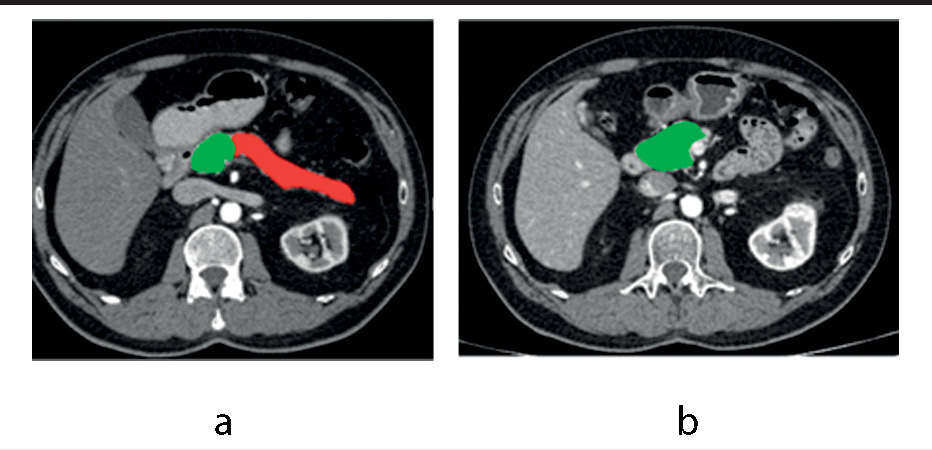

Объем удаляемой и остающейся ткани ПЖ определяли по данным мультисрезовой компьютерной томографии (МСКТ) с болюсным контрастированием, выполненной до операции и через 3, 6 мес после нее. Анализ полученных диагностических изображений и волюметрия выполнялись с помощью лицензионного программного обеспечения Vitrea и Видар-Инфорад 3.0 Dicom Viewer. Объем удаляемой ткани представлял разность между исходным объемом и остаточным. Результаты получены у 39 (81,3%) пациентов (рис. 1).

Рис. 1. Пример результатов МСКТ: а – предоперационное исследование, аксиальный срез на уровне L1 (КТ-срез с неполной визуализацией головки железы для демонстрации дистальных ее отделов), поздняя артериальная (панкреатическая) фаза, волюметрия – зеленым выделена сохраняемая часть ПЖ, красным – удаляемая; b – через 6 мес после операции, аксиальный срез на уровне L2 (головка железы визуализирована в наибольшей ее площади), поздняя артериальная (панкреатическая) фаза, волюметрия – зеленым выделена культя ПЖ. / Fig. 1. CT processing: a – preoperative analysis. Axial CT scan, late arterial (pancreatic) phase: green – pancreatic remnant, red – resected part; b – CT scan at 6 months after the operation. Axial CT scan, late arterial (pancreatic) phase: green – pancreatic remnant.